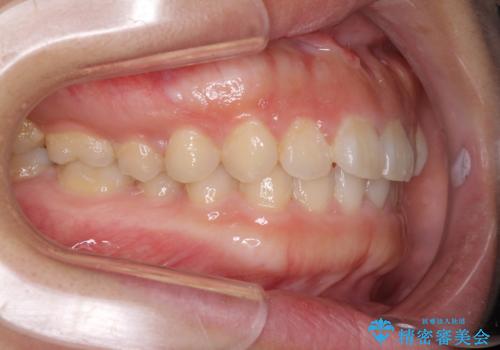

- 前歯のデコボコを治したいとのことで来院された患者様です。

上下顎ともに歯列全体の側方拡大とIPR(歯と歯の間を削る)によってデコボコが解消するように設計し、インビザラインにより治療を行うこととしました。

後方移動に際し、残っていた上顎の親知らずを抜歯することとしました。